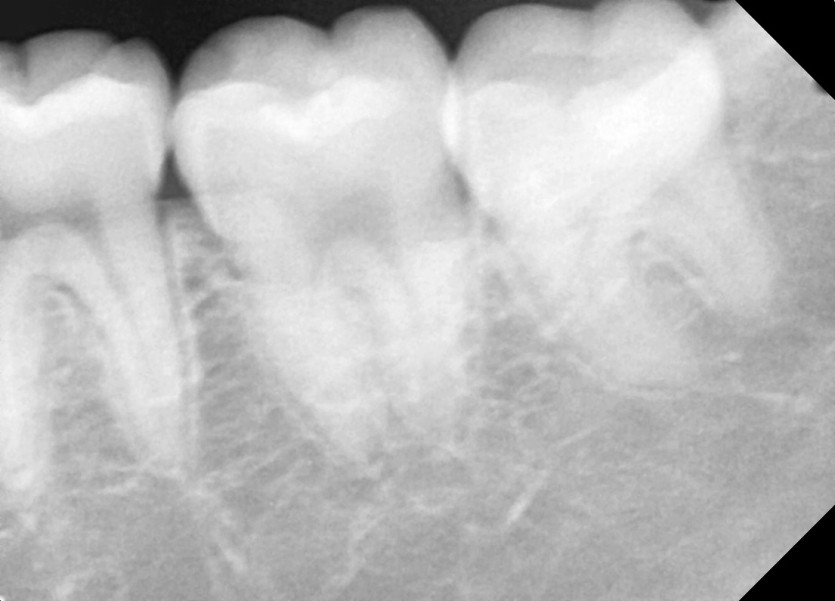

#38 사랑니 발치

구강 외과 전문의가 당일 발치했습니다.